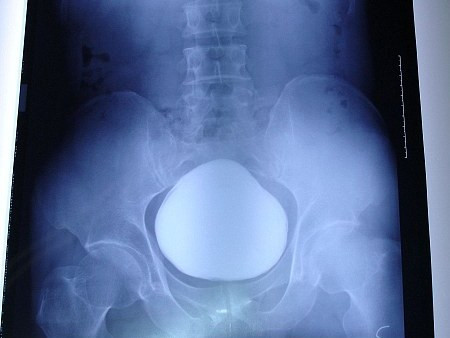

| Ảnh chụp X-quang thấy rõ cục sỏi khổng lồ. Ảnh: Chinanews. |

Bệnh nhân họ Trương, 43 tuổi, được đưa tới bệnh viện thành phố Vũ Hán để khám sau khi ông than thở rằng việc tiểu tiện ngày một đau đớn và khó khăn.

Các nhân viên y tế đã tiến hành chụp X- quang cho ông và họ đã sửng sốt khi phát hiện một vật thể khổng lồ rộng 11 cm nằm gọn trong bàng quang của bệnh nhân.